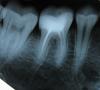

олег1965 Опубликовано 27 августа, 2009 Поделиться Опубликовано 27 августа, 2009 Здравствуйте! кариес на медиальной поверхности действительно есть. Медиальные каналы не допломбированы. Прогноз зависит от того, насколько тщательно были обработаны и промыты каналы. Снимки во время лечения делать надо.Привкус может быть от недополированной пломбы, если где-то остался неудалённый во время полировки гибридный слой. 1 Ссылка на комментарий

Bier Опубликовано 27 августа, 2009 Поделиться Опубликовано 27 августа, 2009 каналы запломбированы плохенько. Не ужасно конечно, но плохенько весьма. На зуб надо было не пломбу ставить, а вкладку и коронку. Но прежде там надо каналы перелечить. На пломбе нависающий край и плохое краевое прилегание (посмотрите внимательно на левую часть зуба по снимку) Ссылка на комментарий

Bier Опубликовано 27 августа, 2009 Поделиться Опубликовано 27 августа, 2009 на 80% там будет гранулема. 1 Ссылка на комментарий